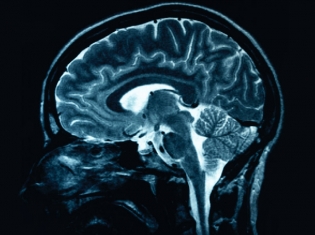

(RxWiki News) With the creation of MRI imaging, doctors and researchers suddenly had a flood of information available, particularly when it came to neurology. The problem was that it was an overwhelming amount of data.

University of Colorado Boulder researchers have created a new software program that lets physicians and scientists combine hundreds of brain images into one. The process could dramatically trim the amount of time physicians spend pouring over images.

Using a statistical process, investigators are then able to produce a consensus "brain activation image" reflecting hundreds of studies at once.